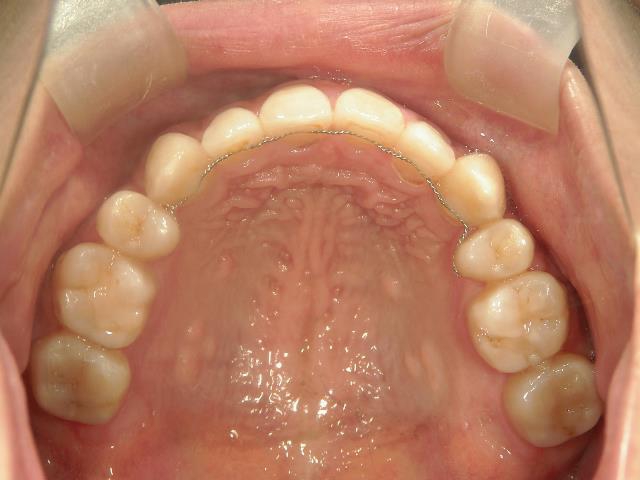

その後、伊藤歯科医院に入社し、やっと矯正をする機会に恵まれました。矯正しているのが目立ちにくい治療を希望し、舌側ワイヤー矯正に挑戦することになりました。

はじめて歯の裏側に器具をつけた時は違和感がとてもあり、特に「さ行」が発音しづらかったのを覚えています。舌が器具に当たりやすいので、傷付きやすく、スペースが狭いため窮屈な感じがしました。

はじめは気になることばかりでしたが、2,3週間するとすっかりと慣れ、しゃべりづらさも改善してきました。それと同時に歯並びも動き始め、月に一回調整をする度に自分で歯の写真を撮って変化を楽しみました。舌側矯正だったので、あまり周囲の人から矯正をしていることを気づかれずに治せたことは嬉しかったです。ずっと悩んでいましたが、矯正をはじめるとあっという間に時間が過ぎていきました。